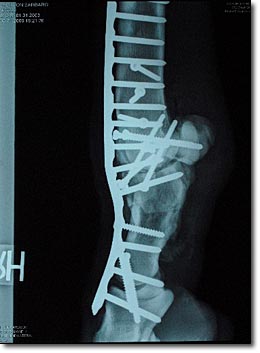

My child has not undergone brain surgery – not even close, Delaney would be the first to remind me – but I can tap into his and Leah’s anxiety during the procedure. In 2007, we found out that my son Alex needed a second surgery for his broken ankle. This time, the orthopedist would insert nails. I had visions of the x-rays of what they did to the racehorse Barbaro’s broken leg.